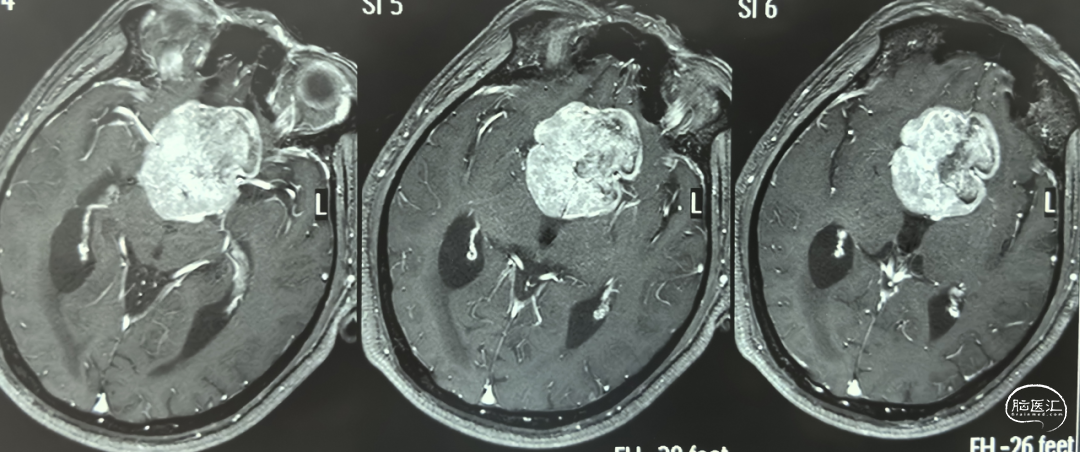

术前增强MRI